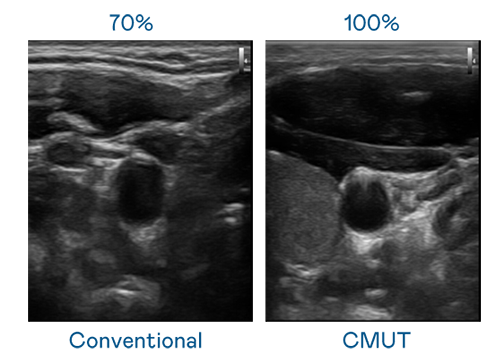

CMUT 技术是一种用电容式微机电元件来产生超音波讯号的技术。与传统 PZT 压电式技术相比,CMUT 频宽增加 30%,更宽频的超音波讯号让影像解析度大幅提升,是实现高影像品质医疗超音波扫描、促进精准医疗发展的关键技术。

大频宽带来超清晰影像

超音波影像的解析度高低,首先取决于探头能发出的讯号频宽。天九娱乐 CMUT 可提供高清晰的超音波讯号,提供高频宽、高灵敏度、影像纹理细节更高的超音波影像,协助医护人员缩短影像判读时间及利用精准的医疗影像进行诊断。